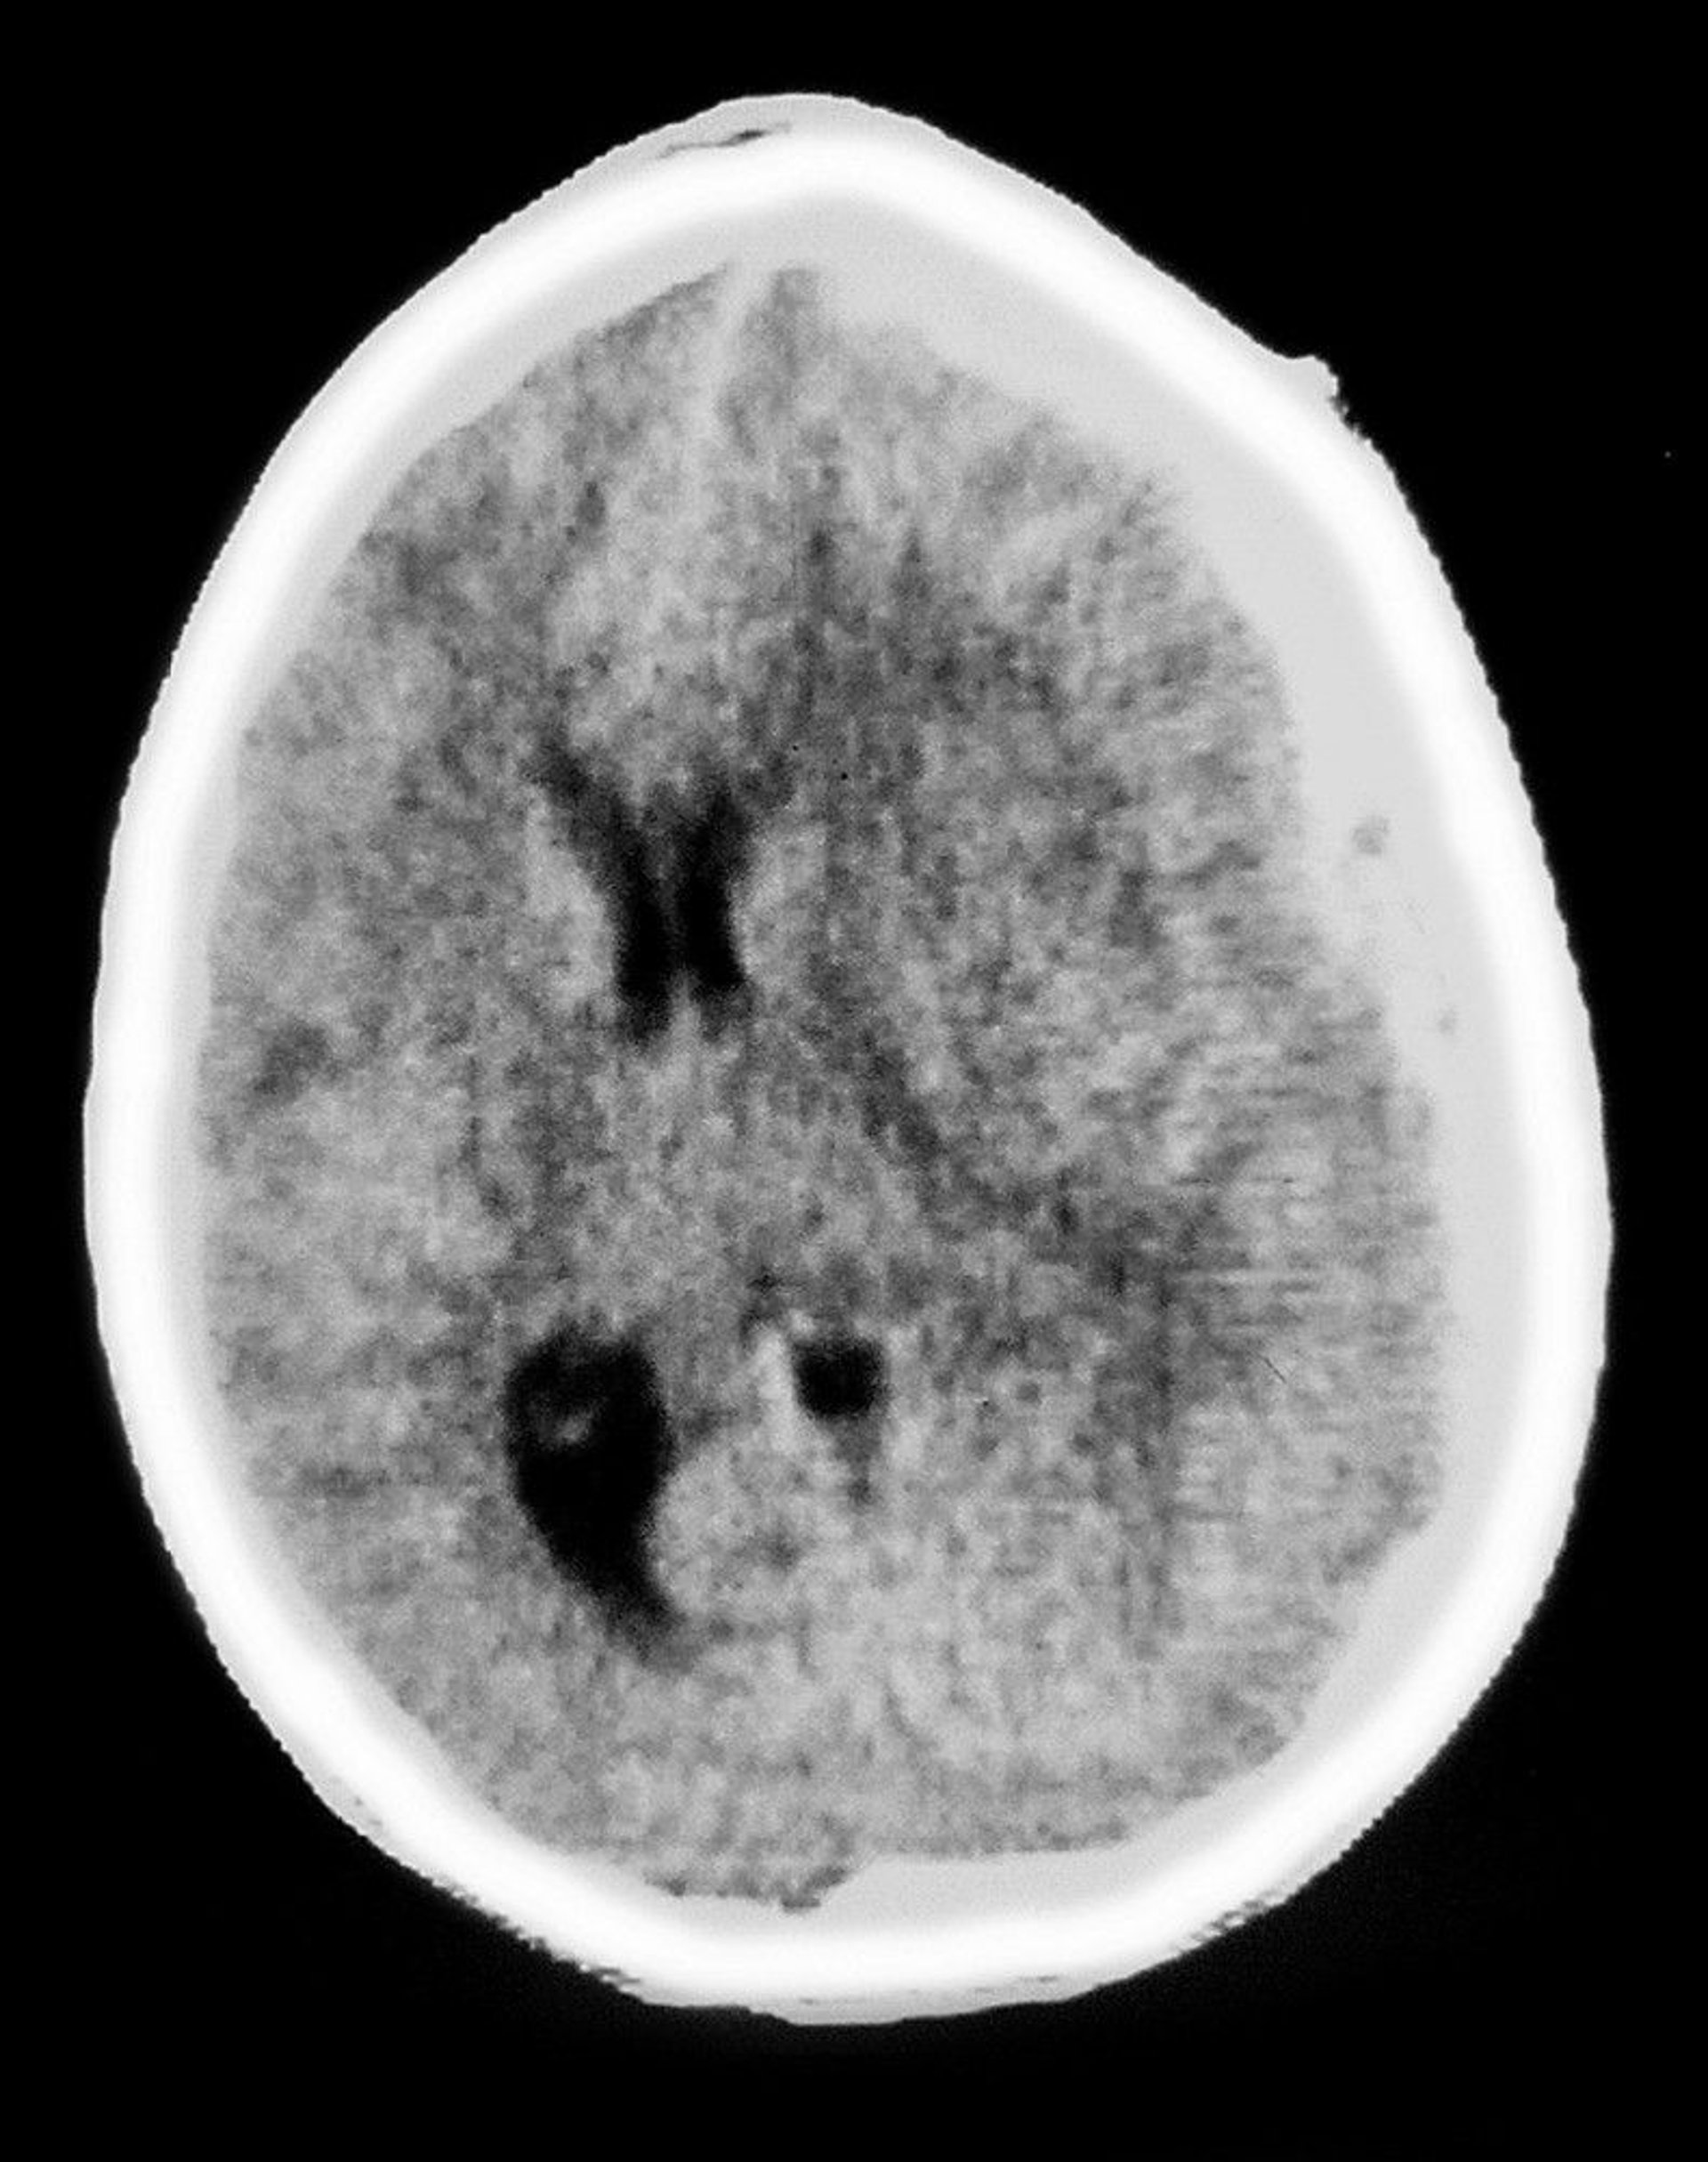

Subduralhämatom

Diese CT-Aufnahme zeigt eine halbmondförmige Trübung über dem Hirngewebe, die für ein subdurales Hämatom charakteristisch ist. Es gibt auch eine Raumforderung mit Ventrikelkompression und Mittellinienverlagerung.

Cavallini James/BSIP/SCIENCE PHOTO LIBRARY